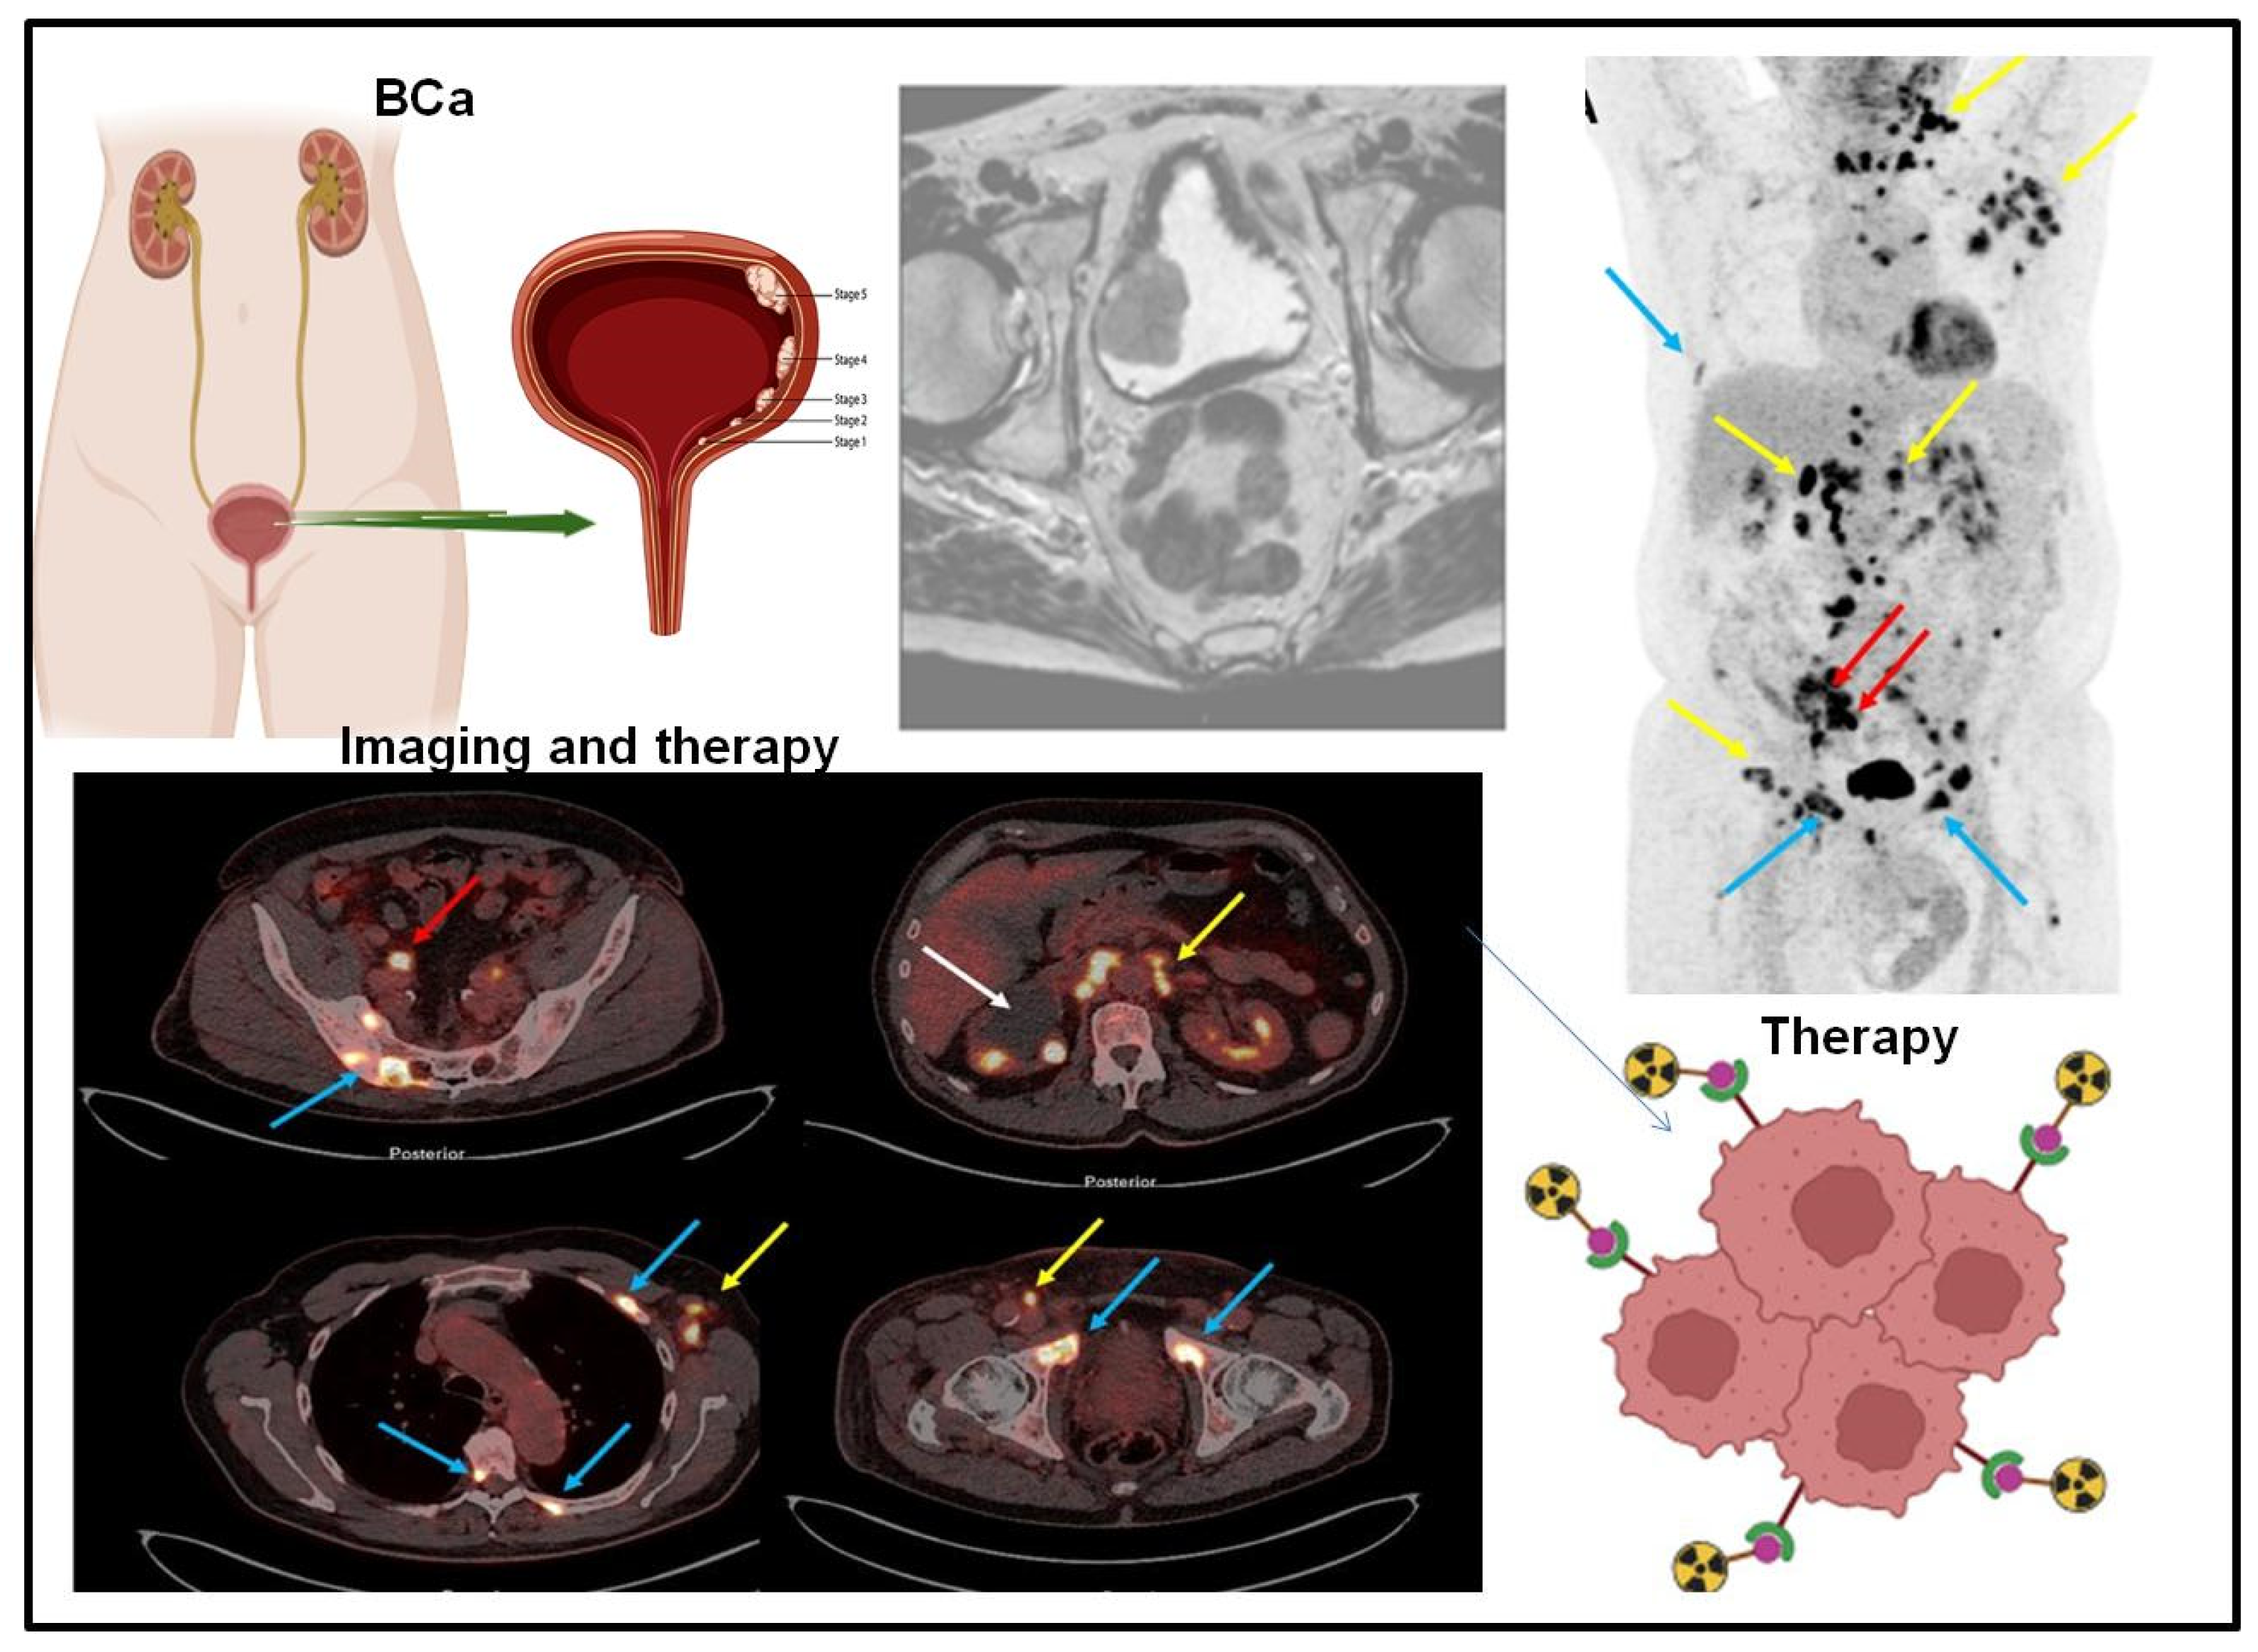

3. Targeted Molecular Imaging of Bladder Cancer

4. Integration of Mass Spectrometry and Molecular Imaging for Bladder Cancer Biomarker Detection as Advancing Precision Oncology